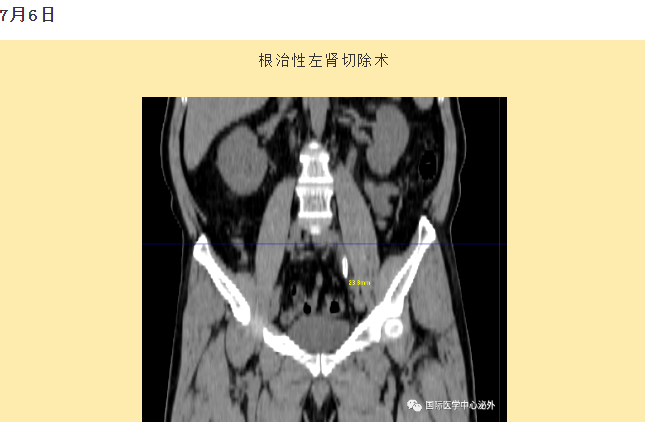

西安國(guó)際醫(yī)學(xué)中心醫(yī)院順利完成了達(dá)芬奇Xi(第四代)機(jī)器人裝機(jī)。7月6日—7月15日,泌尿外科成功完成了達(dá)芬奇Xi(第四代)機(jī)器人手術(shù)6例,標(biāo)志著科室微創(chuàng)外科邁入新時(shí)代,造福萬(wàn)千患者。